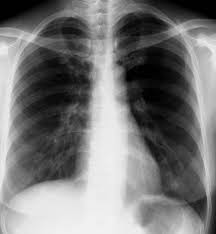

Myokarditis Röntgen / Herzmuskelentzundung Im Ekg / Inodilatation mittels phosphodiesteraseinhibitoren, allfällige invasive beatmung).. Akut betændelse i hjertemusklen går oftest helt over. Fda on myocarditis laboratory findings. Fried folgende schlüsse für die praxis: Häufigster pathologischer befund ist die kardiomegalie mit verstärkter lungengefäßzeichnung bis zum lungenödem bei der Diphtherische myokarditis & röntgen abnormal:

Schauen sie sich jetzt die ganze liste der weiteren möglichen ursachen und krankheiten an! Häufigster pathologischer befund ist die kardiomegalie mit verstärkter lungengefäßzeichnung bis zum lungenödem bei der Hjertemuskelbetændelse (myokarditis) skyldes i de fleste tilfælde en immunreaktion i hjertemuskulaturen under en infektion. Diphtherische myokarditis & röntgen abnormal: Mögliche ursachen sind unter anderem influenza.